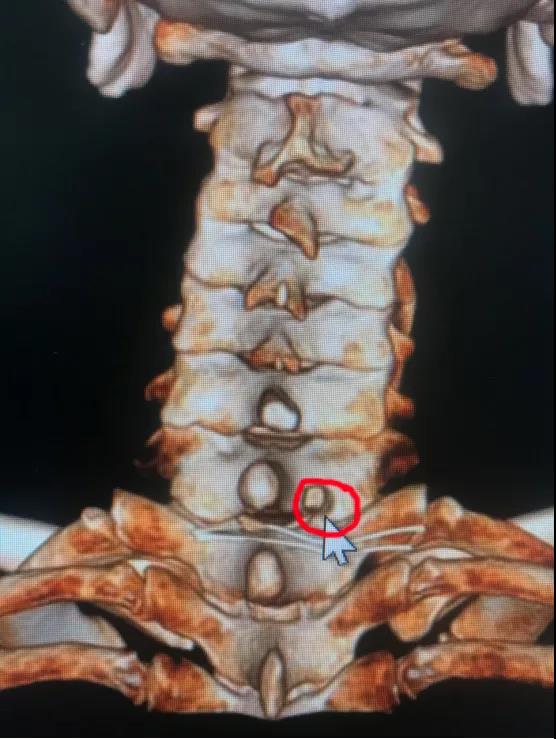

颈椎前路间盘摘除椎管减压植骨融合内固定(ACDF)是经典的手术方式,但要牺牲一个颈椎运动节段。近日,*安泰**市中心医院脊柱外科收治宁阳患者张某,45岁,颈部不适2月,右上肢疼痛麻木1月余。采用牵引、药物等治疗,效果欠佳。疼痛无法缓解,严重影响睡眠。入院诊断颈椎间盘突出症,完善X线、CT、MR相关检查显示:颈6/7椎间盘突出,向下方脱垂至颈7椎体中下方,压迫脊髓。由于颈椎椎间盘突出高度脱垂,至椎间隙下方较远,采用传统ACDF,从前方椎间隙根本无法取出脱垂的间盘组织。科室采用局部麻醉,颈椎后路“钥匙孔”技术,通过在颈7右侧椎板用高速磨钻磨出一个7毫米的小孔,直达病变部位,将高度脱垂的间盘顺利取出,患者术后疼痛即刻消失,由于局部麻醉,增加了手术的安全性,患者术后就能够正常下床活动,手术第2天出院,受到了患者及家属的好评。

神经根型颈椎病是最常见的颈椎病类型,由于颈椎神经根活动度较小,“黄豆”大小的的颈椎间盘突出就可以引起剧烈疼痛,脊柱外科开展脊柱内镜治疗颈椎间盘突出技术(“钥匙孔”技术)已经有3年时间,具有“三好一满意”(1、外观好,颈部后方只有7毫米切口,一般愈合以后看不到切口;2、内镜下视野好,放大约4-10倍,清晰,完全不破坏脊柱稳定性,不需内固定,微创,安全;3、疗效好,通过透视定位,直达患处,直接解除神经压迫;4、患者满意,术后即刻解除症状,早期下地,早期恢复工作生活。)的优势。脊柱外科通过此技术已治愈近100例患者,都收到取得良好的治疗效果。该患者高度脱垂型的颈椎间盘突出采用内镜下颈椎后方椎板“钥匙孔”技术,是在掌握熟练的颈椎内镜技术的情况开展的,此手术的成功开展,标志着*安泰**市中心医院脊柱外科颈椎内镜技术又跨上一个新的台阶。